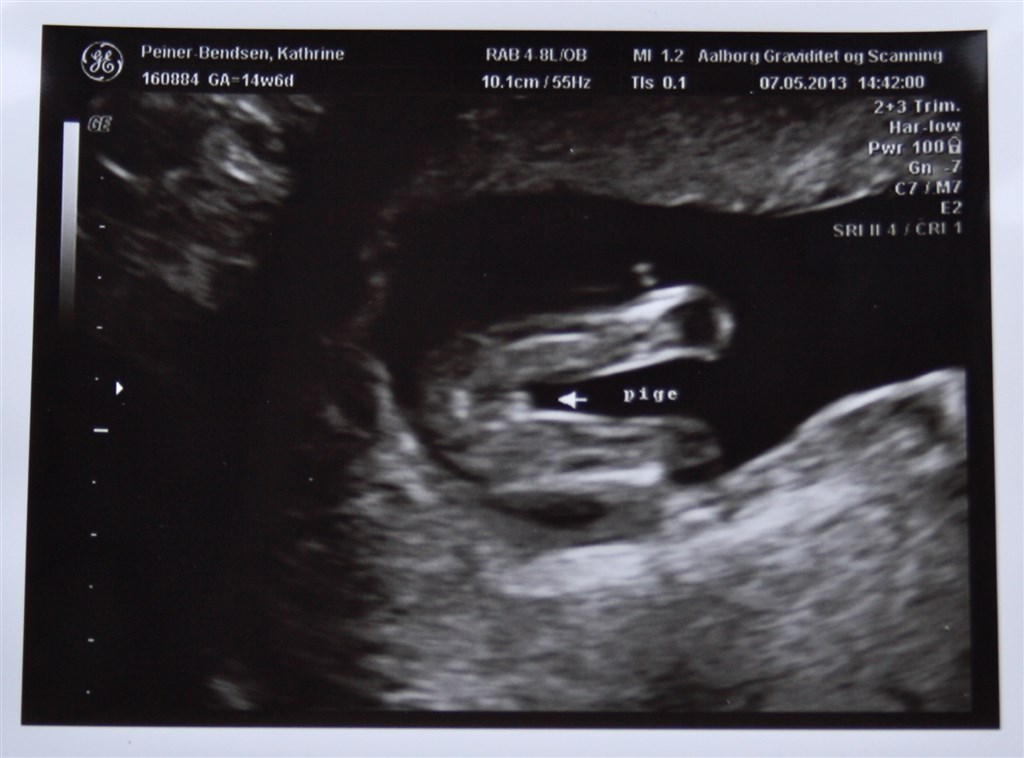

Gæt kønnet. Der er stor tvivl. Uge 12 sagde de pige, men 14 dreng, men de havde meget svært ved at finde pungen og sagde bare at det måtte være en dreng pga tappen.

Bare til sammenligning får du her et billede af min datter fra uge 15 (14+6)

Vedhæftede fotos (klik for at se i fuld størrelse)